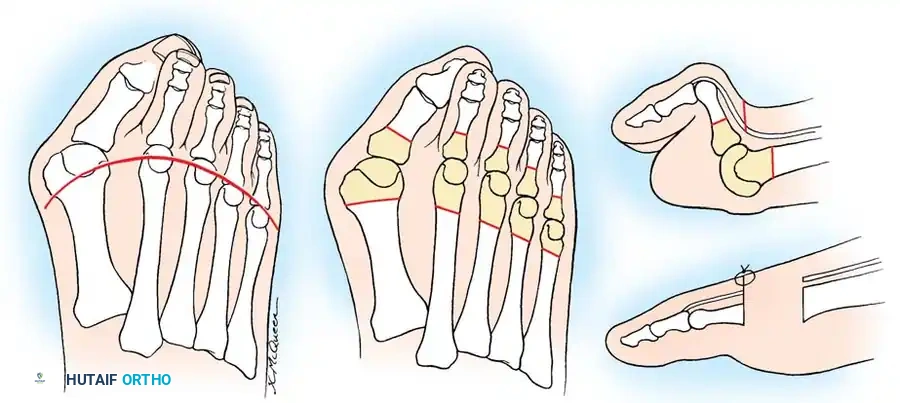

Biomechanics of Forefoot Collapse

Understanding the biomechanical collapse of the rheumatoid forefoot is essential for effective surgical reconstruction. The deformity is driven by a predictable sequence of intrinsic and extrinsic muscle imbalances:

- Intrinsic Muscle Dysfunction: As the MTP joints subluxate dorsally, the intrinsic muscles (lumbricals and interossei) shift dorsal to the flexion-extension axis of the MTP joints. Consequently, they lose their primary ability to flex the MTP joint. Furthermore, their secondary function—extending the proximal interphalangeal (PIP) and distal interphalangeal (DIP) joints—is severely weakened.

- Extrinsic Overpowering (Tenodesis Effect): With the intrinsics mechanically disadvantaged, the extrinsic long toe flexors (flexor hallucis longus and flexor digitorum longus) exert an unopposed pull, drawing the PIP and DIP joints into rigid flexion.

- Extensor Mechanism Concentration: The inability of the extensor digitorum brevis (EDB) and extensor digitorum longus (EDL) to extend the middle and distal joints compounds the deformity. Because of reduced tendon excursion secondary to MTP joint hyperextension, all the extension moment of the extensor hallucis longus (EHL), extensor hallucis brevis (EHB), EDL, and EDB is concentrated entirely at the MTP joints.

Fig. 81-7 Biomechanical progression. (A) Normal alignment and balance of the MTP joints and extensor sling. (B) Progressive dorsal subluxation and lesser toe deformity. (C) End-stage deformity with complete MTP dislocation; the proximal phalanx is ankylosed to the dorsal aspect of the metatarsal head, and the plantar fat pad has migrated distally.

Gradually, this concentrated extension force completely dislocates the MTP joints. At end-stage disease, the proximal phalanx rests entirely on the dorsal aspect of the metatarsal neck.